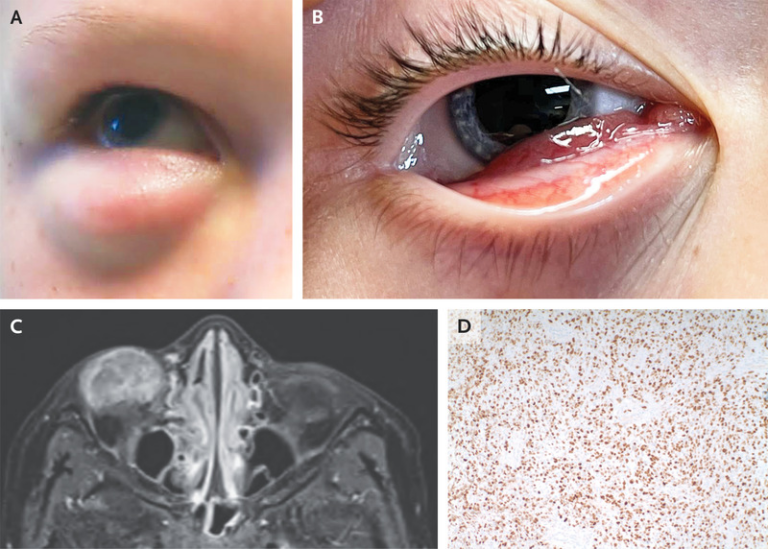

Cancers | Free Full-Text | Optimizing Rhabdomyosarcoma Treatment In

www.mdpi.com

www.mdpi.com

Primary Orbital Rhabdomyosarcoma In A Child

article.sapub.org

article.sapub.org

rhabdomyosarcoma eye orbital orbit child ure mass fig soft showing right

(PDF) Embryonal Rhabdomyosarcoma Of The Orbit In A Child.

www.researchgate.net

www.researchgate.net

orbit embryonal rhabdomyosarcoma child